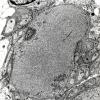

PERIPHERAL NEUROPATHY

5 AXONAL REGENERATION (6)